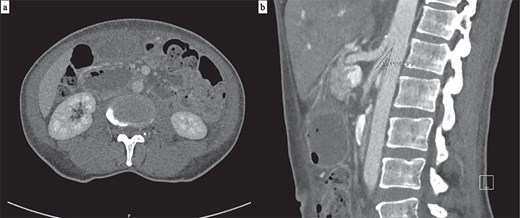

Abdominal computed tomography (CT) showed marked dilation of the stomach, first and second duodenal segments, with abrupt collapse at the retroperitoneal junction between the second and third duodenal segments. The aorto-mesenteric angle was reduced at 22° (Fig. 1), and no intraluminal cause of obstruction was visualized. The CT report subsequently concluded the duodenal obstruction was caused by SMA syndrome.

(a) Axial CT demonstrating a grossly distended stomach, first and second duodenal segments with collapse at the third segment between the abdominal aorta and SMA. (b) Sagittal CT with a measured aorto-mesenteric angle of 22°.